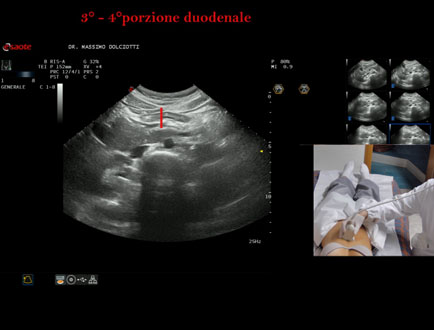

Data inserimento: 19/09/2025

Ecografia del: 10/09/2025

Strumento: Esaote MyLab Eight

Sonda: Convex Multifrequenza 1-8 MHz

Età Paziente: F 24 anni

Motivazione dell'esame:identificazione della terza e quarta porzione duodenale.

Commento all'esame: le immagini ed il video documentano il duodeno ed in particolare la terza e quarta porzione.

Conclusioni: 3° e 4° porzione duodenale (3rd and 4th duodenal portion).

Presentazione: Dr. Massimo Dolciotti - Ancona

Elaborazione digitale: Andrea Dini - Ancona